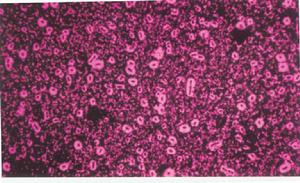

革蘭氏染色法是最常用的鑑別染色法之一。此法起始1881年,染色步驟是先用結晶紫或龍膽紫染液加於已固定好的標本上使之著色,其後加碘液作媒染劑,再用酒精脫色,最後用復紅或沙黃復染。革蘭氏染色的結果與培養基成分、培養條件及操作技術等有密切關係。如塗片太厚影響酒精脫色,革蘭氏陰性菌則可染成革蘭氏陽性菌。脫色時若酒精作用時間太長,革蘭氏陽性菌又會染成革蘭氏陰性菌。在缺乏鎂鹽的培養基中,革蘭氏陽性菌可變成革蘭氏陰性菌。菌齡也能影響染色的結果,這與生長過程中核酸含量的改變有關。革蘭氏染色法的原理還不十分清楚,有化學學說、等電點學說、滲透性學法,目前最通常的解釋是革蘭氏陽性菌在95%酒精中因含粘肽多而導致細胞壁脫水,通透性減低,使在細菌細胞內著色的染料─碘複合物不易透出細胞壁,所以保留了紫色;革蘭氏陰性菌含粘肽少,其細胞壁在95%酒精作用下通透性變化不大,酒精容易進入菌體內溶解染料─碘複合物而透出,失去紫色後被復染成為紅色。

有些細菌,如結核桿菌,不般不易著色,一旦染上色後又不易被鹽酸酒精脫色,稱為抗酸菌。主要步驟是將細菌塗片、乾燥、固定後,以石炭酸復紅染液加溫進行染色,然後用含酸的酒精脫色,最後用美藍復染。一般細菌以及標本中的物質都被脫色,抗酸菌則不能,仍為紅色。在藍色背景上呈紅色的細菌即為抗酸菌。